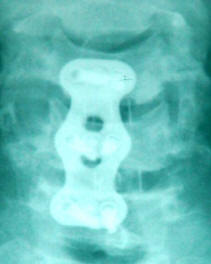

23-MARCH-2010  AHMAD YOUSEF AL-HAIDABY  51 YEARS  EXTRUDED DISC C5-6, C6-7 WITH OCCLUSION OF THE LEFT C6-7 FORAMEN.

MRI cervical spine performed 28-January-2010 showed PCD C5-6 right side and PCD C6-7 left side with foraminal occlusion.

MRI of the cervical spine performed 16-March-2010  showing the same picture seen at the one performed earlier.

Discectomy of C5-6 and C6-7 was achieved with removal of the anterior and posterior osteophytes . The dura was seen at the depth of the fields both sides. PEEK-OPTIMA  cervical cages 14X11X6 mm were inserted at both levels with NANOSTEM synthetic bone paste and using Medtronic Atlantis  2 level plate 45 mm length, fusion of C5-6-7 was done. All stages of the operation were controlled using image-intensifier.

Smooth postoperative recovery, and the power of left upper limb became normal.

Postoperative X-ray showing the construct.